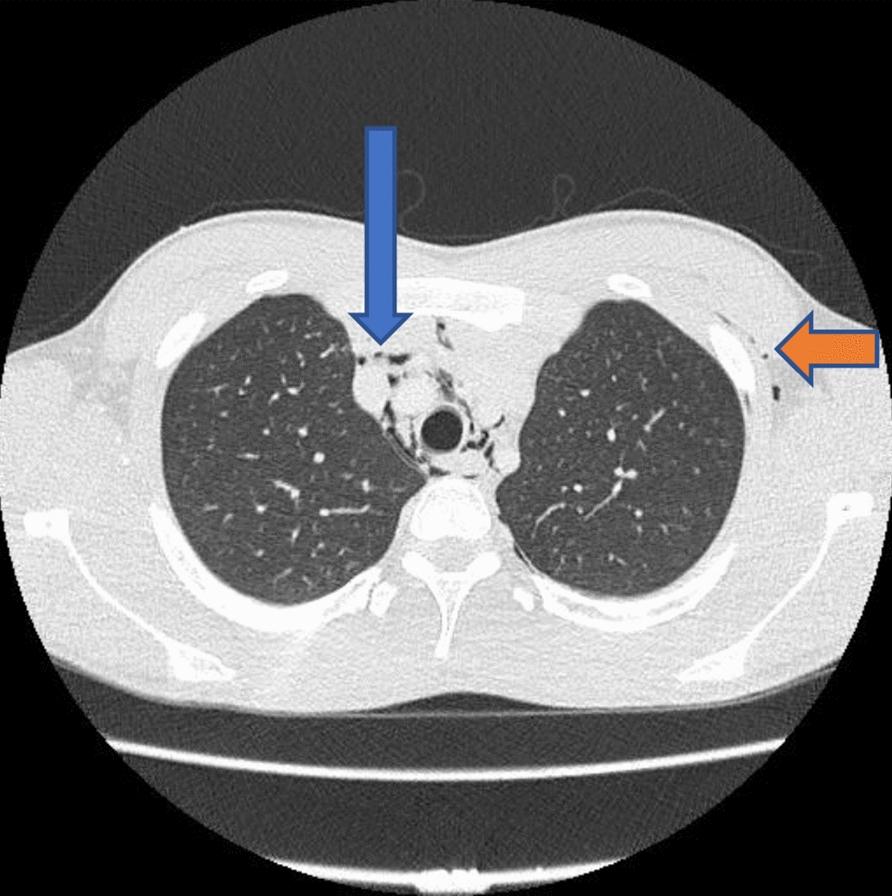

An 18-year-old Caucasian British male patient presented to the emergency department complaining of sharp, central, pleuritic chest pain that radiated up to the throat and was worse on lying down. On examination, palpable surgical emphysema was noted on the neck and was noted on chest X-ray. A computed tomography of neck and chest was then performed, which revealed extensive pneumomediastinum tracking along the cervical, axillary, presternal, and anterior pericardial regions. A water-soluble contrast study was performed, which showed no evidence of esophageal perforation.